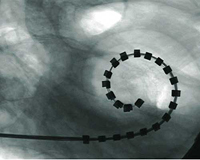

Una vez conozcamos el grado y el tipo de hipoacusia, podremos ofrecer el mejor tratamiento para cada caso; desde los drenajes transtimpánicos, hasta los tratamientos más complejos, como los implantes osteointegrados y los implantes cocleares.

Los problemas del oído externo que pueden causar la hipoacusia van desde los habituales tapones de cera, a problemas menos frecuentes como la atresia congénita de conducto, una malformación que produce una falta de desarrollo del conducto auditivo externo desde el nacimiento. Los niños afectados de atresia congénita pueden beneficiarse de un tratamiento quirúrgico para mejorar la audición: los implantes osteointegrados.

En el oído medio es donde se originan la mayor parte de los problemas auditivos en la infancia. Los procesos infecciosos del oído medio, en ocasiones, necesitan un tratamiento quirúrgico; y muy frecuentemente los pacientes precisan de la colocación de drenajes transtimpánicos.

Más raramente, en los casos crónicos, es necesaria la realización de reconstrucciones del oído medio mediante técnicas de timpanoplastia, con reconstrucción del tímpano o de la cadena de huesecillos con prótesis de oído medio.

La hipoacusia neurosensorial es debida a una alteración del oído interno, ya sea desde el nacimiento o de forma adquirida. En estos casos debemos recurrir a algún tipo de dispositivo electrónico como son los audífonos convencionales. Si los audífonos no son útiles, los pacientes pueden beneficiarse de dispositivos que requieren implantación quirúrgica como los implantes cocleares.